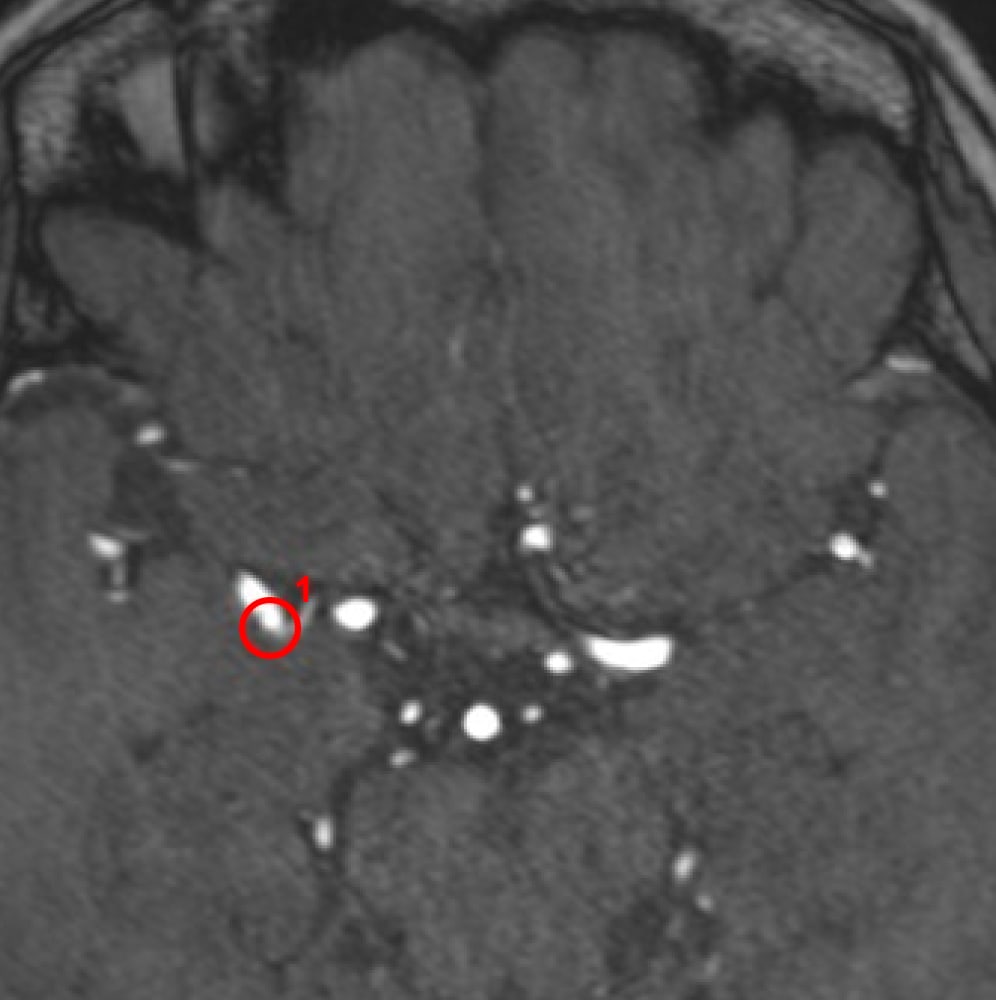

解析事例

中大脳動脈